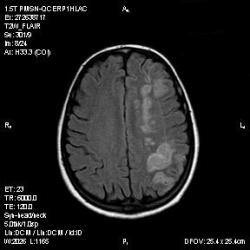

Из анамнеза - Женщина 45 лет. За год похудела на 15 кг (со слов матери), в последние месяцы случались эпизоды потери сознания. Онкозаболеваний и прочая в анамнезе нет. Сознание спутанное, из особенностей в анализах только подъем амилазы крови.

К сожалению, не владею методом КТ, но учитывая наличие неравномерного уплотнения в мозговых структурах с элементами очаговых "вкраплений", единственное, что приходит на ум - это рассеяный склероз. Хотелось бы уточнить, что беспокоило пациентку в течение последнего года кроме потери веса и эпизодов потери сознания? Была ли какая-либо очаговая неврологическая симптоматика? Отмечались ли какие-либо расстройства в двигательной или чувствительной сфере и т.д.? С уважением Helenmar.

И это точно не РС, т.к. характер очагов другой, ни один из них не копит контраст, нет субтенториальных очагов (извиняюсь, я этого в сообщении не указал), нет клиники.

"Раскрою" карты. Мы подумали о синдроме MELAS (mitochondrial encephalomyopathy, lactic acidosis and stroke) - дословно, митохондриальная энцефаломиелопатия, лактоацидоз и инсульт. В качестве дифференциальной диагностики можно было бы предположить вирусный энцефалит, но опять-таки, расположение очагов смущает - только с одной стороны и в абсолютно различных структурах.

В данном случае мы видим импульную последовательность FLAIR - режим с подавлением сигнала от воды, поэтому ликвор гипоинтенсивен, а также (вторая серия) - изображения, взвешенные по T1 после введения контрастного препарата. На T1 жидкость (ликвор) также представляется гипоинтенсивной. Зато на этих сериях гиперинтенсивны сосуды, т.к. контрастное вещество циркулирует в кровяном русле.

Изменения носят сосудистый характер. Процесс достаточно острый, имеется объемное воздействие, борозды левой гемисферы компремированы. По поводу MELAS синдрома очень сомневаюсь, почему поражена только левая гемисфера? Надо делать МР-ангиографию, смотреть нет ли стеноза

MELAS синдром - дебютирует с детских лет, характерен целый комплекс неврологических проявлений, заболевание генетическое, поражение системное, хотя есть множество вариантов митохондриального поражения, все же сомнительно. Хотелось бы акцентировать внимание, что гиперинтенсивные очаги есть в мозолистом теле, поражены выражено перивентрикулярные отделы, U -пути, белое вещество, поэтому так категорично демиелинизацию не вычеркивала бы из дифряда ( хотя тоже нетипично односторонее поражение). Думаю, для объективных выводов все же мало общей информации о пациентке, были ли клинические эпизоды раньше, чем объяснить такую потерю веса (возможно есть проявление паранеопластического синдрома?). Ну и МРТ-контроль в динамике, ангиография.

Да, неоднозначный случай. Точно не РС и не ОНМК. Я бы написала асимметричную лейкоэнцефалопатию неясного генеза. Можно было бы думать о лимфоме (полифокальное поражение, да еще мозолистое тело вроде бы задействовано (эх, сагиттальчики бы)). Но! Учитывая отсутствие накопления КВ.... Ну и надо исключать интоксикацию, всяческие аутоиммунные процессы (в т.ч. и васкулиты), сахарный диабет, ну и естественно наследственную патологию обменных процессов. УУУх! Вот.......

Имхо ишемический онмк в бассейне сма. Особенно показательны 5-й и 6-й файлы, отграничение как раз на границе бассейнов средней и перикаллёзной. Плюс одностороннее поражение.